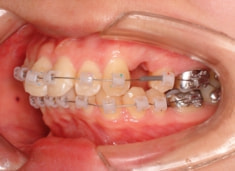

治療開始から1年7ヶ月後